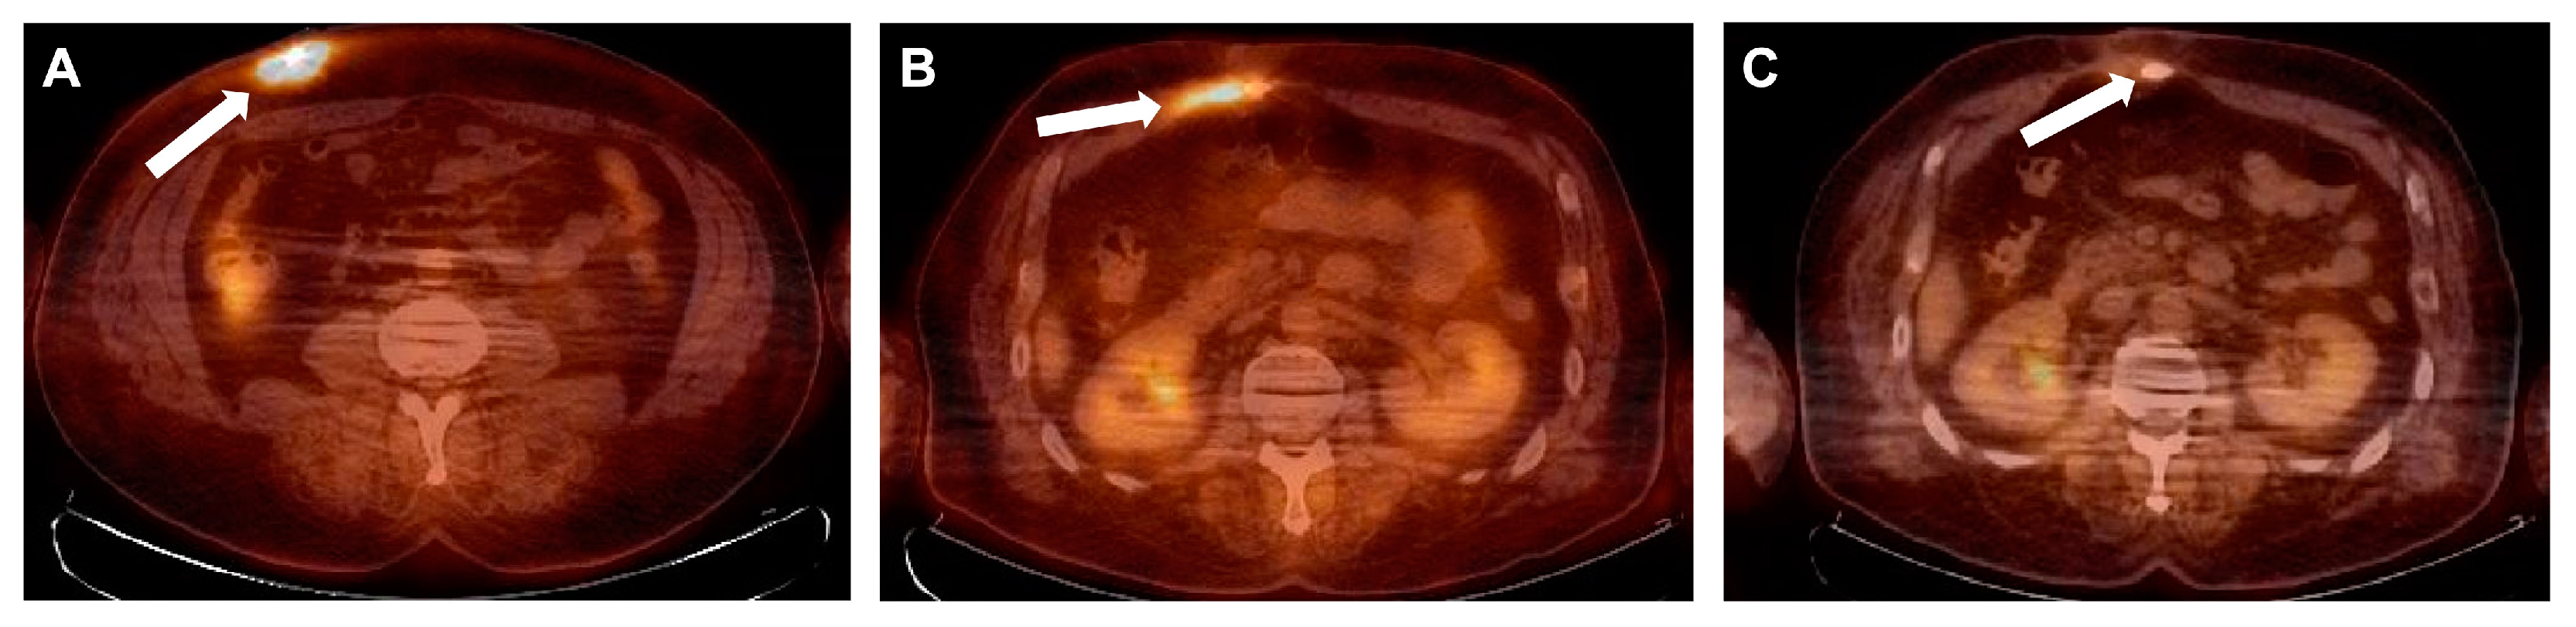

Nineteen weeks later, in March 2021, the patient was hospitalized again due to increased purulent discharge and fistula formation along the driveline (Figure 1B). The results of the wound swab showed the presence of multidrug-resistant (MDR) P. aeruginosa with no alternative oral antibiotics available. Intravenous antibiotic therapy with colistin was initiated with a loading dose of 9 million and then 3 million international units (IU) three times a day and continued until surgical intervention. A decision was made to prepare the patient for driveline repositioning. Fluorine-18-fluorodeoxyglucose positron emission tomography integrated with computed tomography (18F-FDG PET/CT) showed an active metabolic process along the driveline up to the level of the abdominal muscle, with a slight infiltration of the rectus abdominis muscle, representing infection.

Six weeks after the driveline repositioning control, a 18F-FDG PET/CT scan was performed, showing slight residual metabolic activity in the most proximal part of the driveline, but to a lesser extent than before the driveline repositioning (Figure 3B). Considering that PET/CT was performed early after repositioning and most likely represented reactive changes, the wound showed no signs of inflammation, with inflammatory markers (CRP and white blood cell count) within normal limits. The patient was discharged on postoperative day 45.

Thirty-four weeks after the operation, another control PET/CT scan was performed, which showed no signs of significant metabolic activity (Figure 3C). The patient was regularly checked and showed no signs of recurrence 21 months after treatment (Figure 1C).

Figure 3. 18F-FDG FDG PET/CT images. (A) April 2021—condition after implantation of the LVAD. Hypermetabolic changes in the skin, subcutaneous tissue, and muscles along the way of the LVAD cable in the anterior abdominal wall from its entrance gate to the rectus abdominis muscles corresponding to (most likely chronic) inflammation. No other pathological hypermetabolic changes during the whole-body exam or in other implanted devices or cables, and no any dissemination focuses. (B) July 2021—comparison with the previous PET/CT exam; hypermetabolic changes along the way of the LVAD cable are seen to a much less extent but visible near the rectus abdominis muscles and in subcutaneous tissue, most likely representing reactive changes due to recent cable repositioning. (C) February 2022—slight hypermetabolic changes along the way of the LVAD cable are seen with less metabolic activity and extent, but likely without clinical significance. No other dissemination focuses of infection are seen during the whole-body examination. Hypermetabolic changes are indicated with arrows.